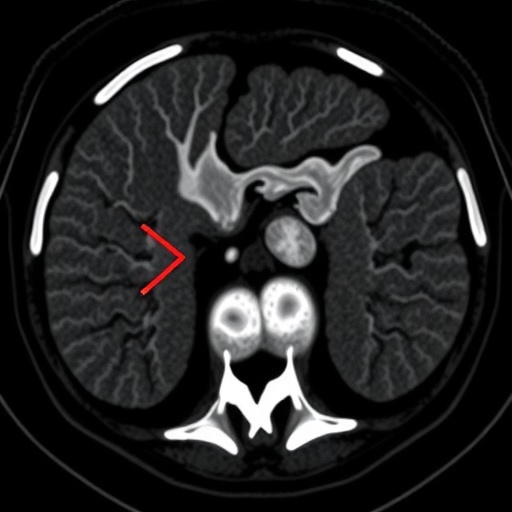

Tumor size varied considerably, ranging from 2.0 to 8.5 centimeters, with an average diameter of approximately 4 centimeters. This variability underscores the importance of meticulous imaging evaluation in identifying lesions at an early stage. On non-contrast computed tomography (CT), most tumors demonstrated a mixed density pattern, with alternating high and low areas suggestive of their eosinophilic and cystic components. This heterogeneous appearance is vital for radiologists to recognize, as it contrasts sharply with the uniform densities seen in other renal masses.

Contrast-enhanced CT scanning revealed even more nuanced information. About 75% of tumors exhibited heterogeneous enhancement, a finding that further delineates the unique vascular architecture of ESC-RCC. Enhancement peaks occurred predominantly during the corticomedullary and nephrographic phases, highlighting dynamic vascular changes as contrast material perfuses the tumor. These imaging phases correspond to early and late post-contrast intervals, respectively, which are critical windows for capturing oncological vascular patterns.

Significantly, all tumors demonstrated distinct boundaries with clear demarcation from surrounding renal parenchyma. This well-defined nature, coupled with the absence of calcifications, necrosis, or hemorrhage, aids clinicians in differentiating ESC-RCC from more aggressive renal cancers known for invasive growth and internal bleeding. Moreover, the lack of lymph node metastasis observed microscopically across all cases offers a hopeful prognosis for patients diagnosed with this subtype.

The study also noted vascular compression in three-quarters of the tumors, indicating that although ESC-RCCs are well-circumscribed, they can exert pressure on adjacent vascular structures. The presence of floating vessels—seen in nearly 88% of cases—within or adjacent to the tumor mass may reflect the tumor’s angiogenic behavior and could serve as an imaging hallmark in clinical practice, guiding surgical planning and risk stratification.

Clinically, this study’s findings reinforce the importance of considering ESC-RCC in the differential diagnosis when encountering well-demarcated cystic-solid renal masses. The unique enhancement pattern—where the degree of tumor enhancement remains consistently lower than that of the adjacent normal renal cortex across all contrast phases—emerges as a signature feature, potentially serving as a non-invasive imaging biomarker for ESC-RCC.